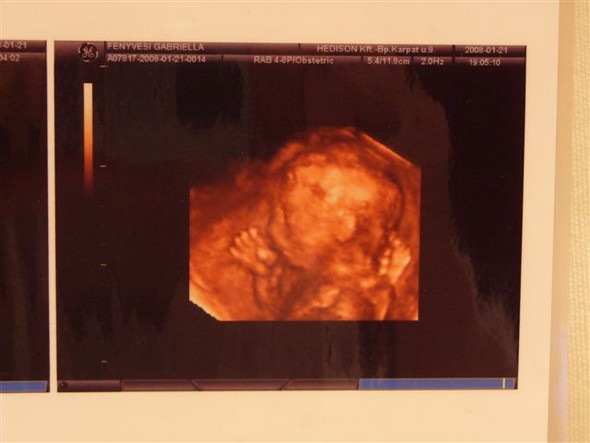

Gabi várunk nagyon az uh-s hírekkel(az érzéseim egyébként azt súgják,hogy kisfiú